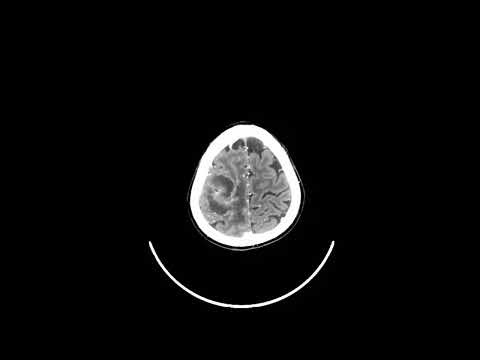

Hellow guys, Welcome to my website, and you are watching Bloodless transsulcal resection for biopsy. and this vIdeo is uploaded by Y Neurosurgery at 2025-04-11T00:42:31-07:00. We are pramote this video only for entertainment and educational perpose only. So, I hop you like our website.